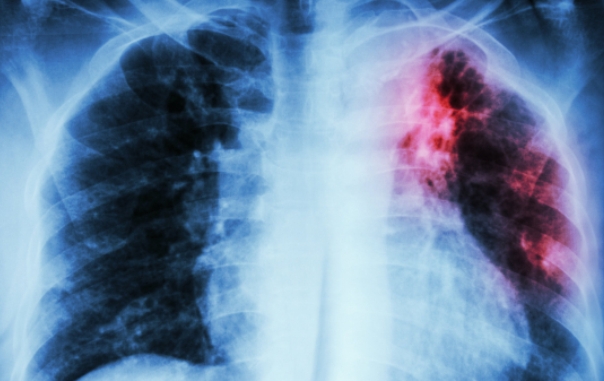

Britanski naučnici utvrdili su kako vrsta luka, porijeklom iz Irana, može pomoći u borbi protiv tuberkuloze otporne na djelovanje uobičajenih antibiotika.

Procjenjuje se kako se rezistentnom tuberkulozom zarazi pola miliona ljudi godišnje.

Sveukupno od tuberkuloze obolijeva 10 miliona ljudi godišnje, uz dva miliona smrtnih slučajeva.